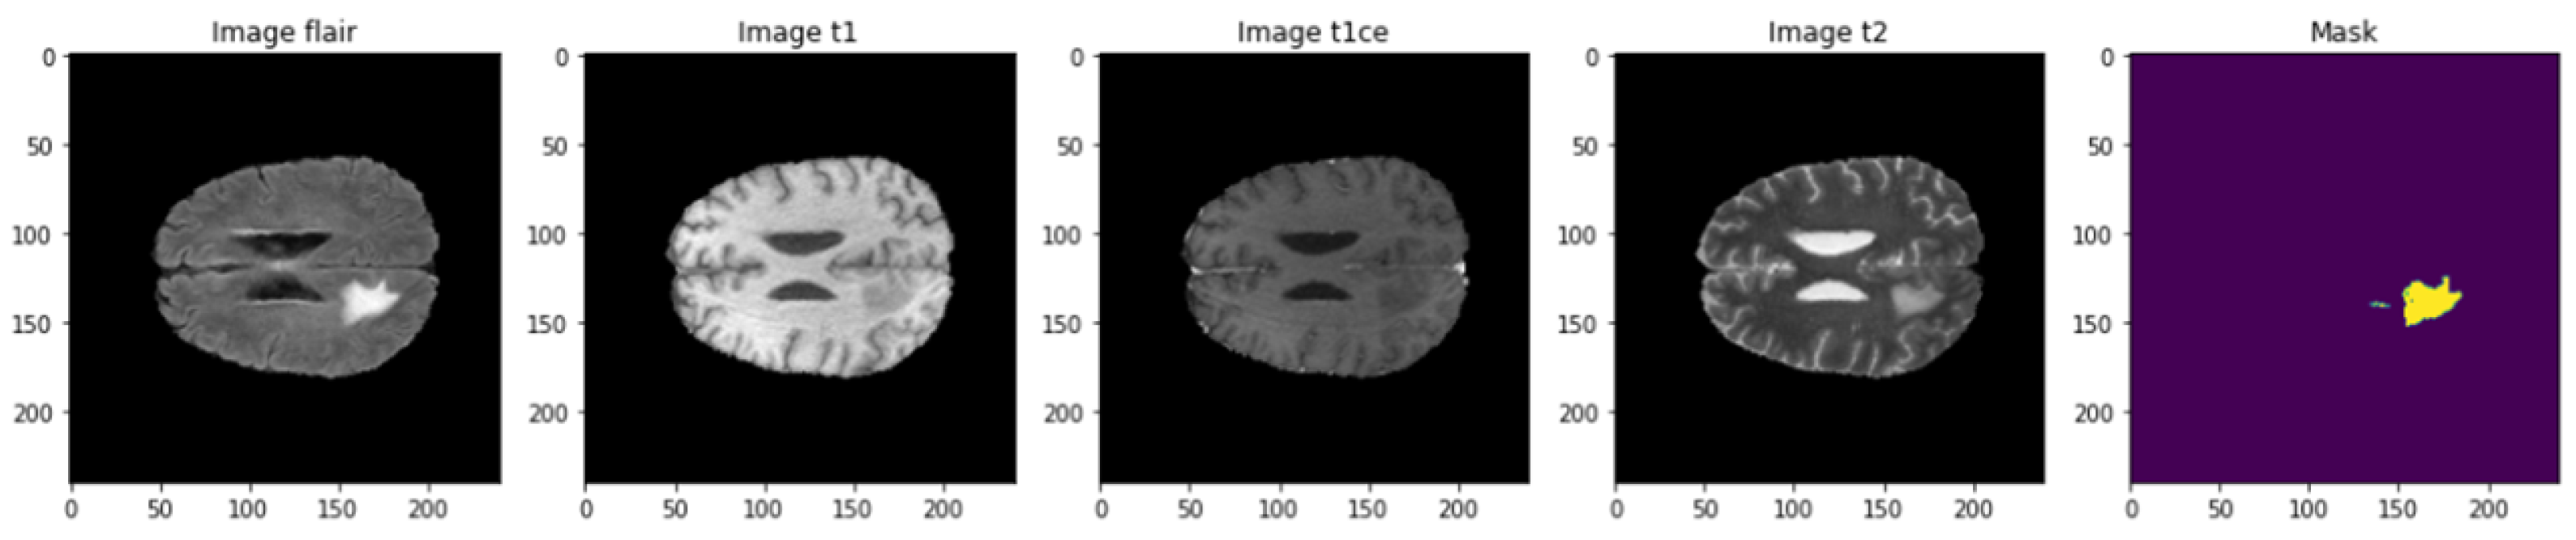

The used dataset is BRaTS 2021 Task 1 Dataset [44]. As training, validation, and testing data for this year’s BraTS challenge, a sizable number of multi-institutional regular clinically acquired multi-parametric MRI (mpMRI) images of glioma with pathologically confirmed diagnosis and accessible MGMT promoter methylation status are used. For Task 1, the datasets utilized in this year’s competition have been updated with many additional routines clinically collected mpMRI scans since BraTS’20. To quantitatively assess the projected tumor segmentations, expert neuroradiologists create and approve ground truth annotations of tumor sub-regions for each patient in the training, validation, and testing datasets. As shown in Figure 3, the dataset is partitioned into a train, validation, and test datasets. Figure 4 illustrates an example of the dataset.

Figure 4.

Example of dataset images.

There are four classes in the segmentation process. Segmentation classes are NOT tumor, non-enhancing tumor (RED color), EDEMA (Green color), and ENHANCING (yellow color). These classes were converted into three classes later. Figure 8 illustrates samples of images and masks with a positive brain tumor. For more precious and fast detection of brain tumor, the 3D U-net segmentation model has been implemented on the BRaTS 2021 dataset. The dataset is divided into 70% training, 20% validation, and 10% testing. Implementation is constructed online on Kaggle. U-net model enhances segmentation validation accuracy up to 99.33%, and validation loss up to 0.01 as shown in Figure 9. We can conclude that our proposed model can detect brain tumor with high accuracy compared to state-of-the-art techniques in terms of classification and segmentation.

Figure 8.

Visualize image with mask of a positive brain tumor.